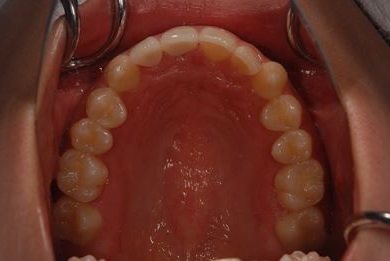

| 性別/年齢 | 女性 / 21歳 | ||||||||||||||||||||||||||||||||

| 主訴 | 歯の変色、欠けた部分を治したい。 | ||||||||||||||||||||||||||||||||

| 治療方針 | 上前歯を根管治療後、オールセラミッククラウンにて審美的回復を行う。 | ||||||||||||||||||||||||||||||||

| 治療内容 | オールセラミッククラウン2本(オールセラミック用土台2本) | ||||||||||||||||||||||||||||||||

| 総治療費 | 286,650円 | ||||||||||||||||||||||||||||||||

| 治療期間 | 4ヶ月 |